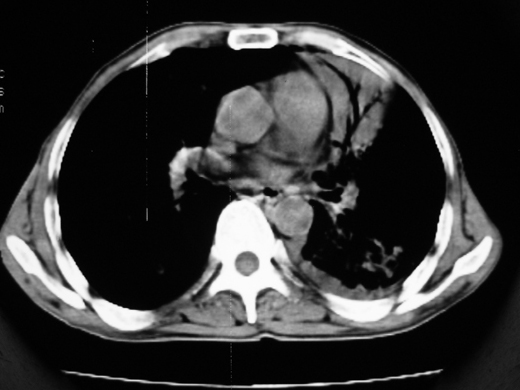

男69岁,年前胸片示肺感染治疗近一月今复查无明显好转,血象正常

右肺多发片絮状结节状及时条索状影,左上肺实变,内可见虫蚀样空洞及支气管气象,左下肺片状及球形病灶,及胸腔积液征象,双肺病灶内多发钙化影,结合病史,考虑双肺继发型肺结核,左胸腔积液

右肺多发片絮状结节状及时条索状影,左上肺实变,内可见虫蚀样空洞及支气管气象,左下肺片状及球形病灶,及胸腔积液征象,双肺病灶内多发钙化影,上纵隔向左侧移位,结合病史,考虑双肺继发型肺结核,左胸腔积液。

考虑双肺支气管内膜结核并左侧肺不张,左胸腔积液可能性大建议气管镜检查或抗结核治疗隔期复查

右肺多发片絮状、结节状及条索状影,左上肺实变,内可见虫蚀样空洞及支气管气象,左下肺片状及球形病灶,有胸腔积液征象,双肺病灶内多发钙化影,上纵隔向左侧移位,结合病史,考虑双肺继发型肺结核,左胸腔积液。 建议结合ppd检查或纤支镜检查!

双肺结核,左肺实变。左侧胸腔积液(部分包裹)。

右肺可见大片状、云絮状改变。右肺可见散在类圆形影,以外带多见。左肺实变,其内可见明显支气管走行影。纵隔淋巴结有增大,左侧胸腔积液。考虑1、肺结核;2、肺癌肺转移不除外;3、左侧胸腔积液。